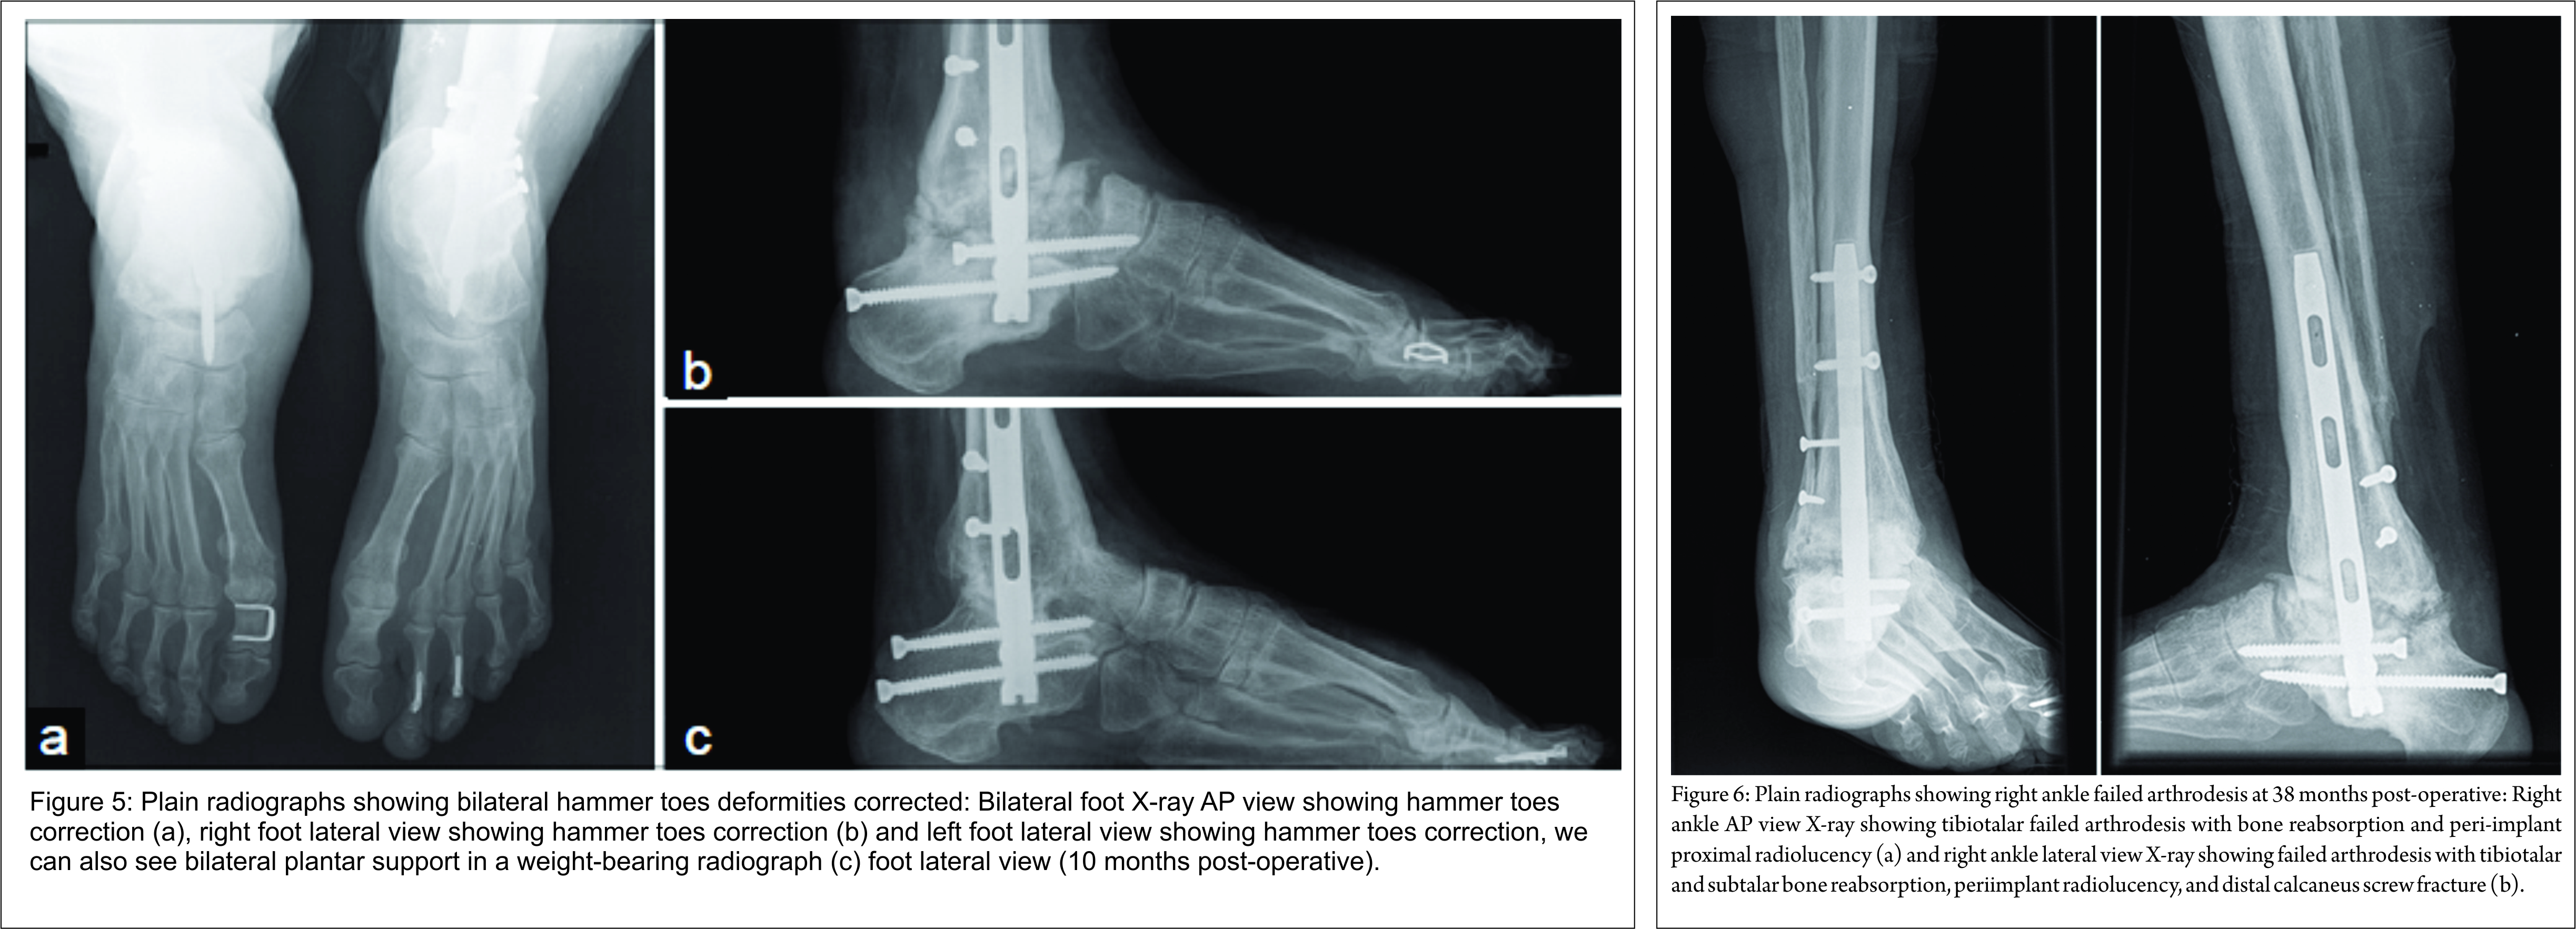

At 12 months after the first surgery, we documented recurrent dorsal proximal interphalangeal (PIP) joints inflammation with shoe wear. Right foot Moberg osteotomy, resection arthroplasty of PIP joints, and flexor tendon tenotomy of all the lesser toes were performed. Left foot Moberg osteotomy, PIP joints fusion of the 2nd and 3rd toes with intramedullary guide implant (Ipp-On® – IntegraTM), PIP joints resection arthroplasty of the 4th toe, and flexor tendon tenotomy of all the lesser toes were performed 14 months after the index surgery. Hardware-related pain caused Moberg osteotomy staple removal at 6 weeks post-operative (Fig. 5). The rehabilitation protocol included progressive weight-bearing with walking boots and lower limb drainage for 6 months. Prophylactic human immunoglobulin therapy was initiated after the last surgery. She regained walking capacity with balanced shoes and returned to work 4 months after left foot surgery. AOFAS score improved to 61 points. No toes related complaints, pressure ulcers or terminal necrosis of the toes were found. At 24 months after initial surgery, she complained of right ankle pain de novo with weight bear and local swelling. Radiologically, failed arthrodesis with tibiotalar and subtalar bone reabsorption, peri-implant proximal radiolucency, and distal calcaneus screw fracture were shown. No local drainage or blood test infection parameters were found. Only symptomatic treatment and nonsteroidal anti-inflammatory drugs were prescribed. At 38 months of follow-up, the patient refers no significant right ankle pain, and no SCLS attacks recurrence was registered (Fig. 6).

This high-risk patients and the unpredictable course of the disease required a multidisciplinary treatment options discussion. The patient never accepted irreversible autonomy loss and was aware of all the possible negative surgery consequences when she signed the surgery consent. There are few treatment options for long-term sequelae of compartment syndrome that include arthroscopic assisted arthrodesis, fusion with an external fixator or internal devices such as plates or intramedullary nails. Arthroscopic arthrodesis is an excellent option when sparing the soft tissues is needed; however, this correction is limited to mild deformities. External fixation represents a serious risk of pin tract infection with no consensus about prevention treatment [8], and therefore we advocate as a potential risk for SCLS relapse. Fusion with plate and screws implies a considerable aggression to the already damaged soft tissues, although it represents a high stiffness construct. The authors managed this clinical case as an equino-varus-cavo-adductus deformity after lower extremity compartment syndrome. Retrograde nailing avoided extensive striping and Berend et al. have demonstrated better biomechanics stiffness compared to crossed screws [9]. Wang et al. [6] described excellent satisfaction rate after retrograde nailing for lower extremity compartment sequelae. No tendinous transfers were considered due to neurological deficit, scarred muscles, and stiff joints. Claw toes deformity has a high risk of pressure ulcers by shoe wear conflict. Local infection in SCLS patients may represent a potential trigger for relapse and therefore must be corrected. Considering the stiff interphalangeal joints, hallux claw deformity was managed by bilateral Moberg osteotomy. Lesser toes were addressed by resection arthroplasty of PIP joints with the exception of the stiffer left second and third toes that were fixated with an intramedullary guide implant [10]. Fusion rate of only 50% (1/2 ankles) was low compared to another published study that shows rates around 91% of the primary bony union after bilateral ankle arthrodesis. However, none of these patients had post compartment syndrome ankle deformity and related sequelae [11]. With no signs of infection, late failed arthrodesis may be related to compartment syndrome, local vascular and neurological damage, technical error or even SCLS per se. Three minor complications were registered. One large posteromedial blister required skin grafting 6 weeks after right ankle procedure. A left ankle lateral surgical wound dehiscence healed by secondary intention only with dressing changes. Failure of left hallux Moberg osteotomy staple was managed by hardware removal. These complications are relatively common and have been previously described in foot and ankle deformity correcting arthrodesis [6, 12]. They are usually due to poor skin and vascular conditions. No delayed weight bearing was noticed in rehabilitation program due to prompt and successful treatment. Concerning deformity correction, the results were very satisfactory. The AOFAS score increased from 20 to a total of 61 points even after tibiotalocalcaneal arthrodesis that does not allow any hind foot movement. Moreover, the painless plantar support permitted walking without crutches after 24 months confined to wheelchair. Returning to work was also an important milestone for this patient. At 38 months of follow-up, the patient is now asymptomatic with minor local right ankle edema and no walking limitation. Radiologically, the bone reabsorption appears to have stabilized (Fig. 6). Anecdotal evidence has shown good results in ankle arthrodesis revision after compartment syndrome [6]. However, one must consider unpredictable consequences of fusion revision in a SCLS patient, including a severe attack during the anesthesia or post-operative infection with potential lethal consequences. This patient has been diagnosed with idiopathic form of SCLS. Although no direct cause was identified, she had been taking azithromycin for a respiratory tract infection which may represent a potential trigger [4, 13]. Monoclonal gammopathy was also present at follow-up lab blood tests as seen in more than 90% of cases [2, 4]. There are several possible prophylactic treatments, which include B2-agonists, thalidomide, calcium channel blockers and chemotherapy with limited evidence considering the rarity of the disease. Intravenous immunoglobulin was administered in the past 12 months of follow-up with no relapses adding to the hypothesis that this may represent an effective prophylaxis [4, 14].